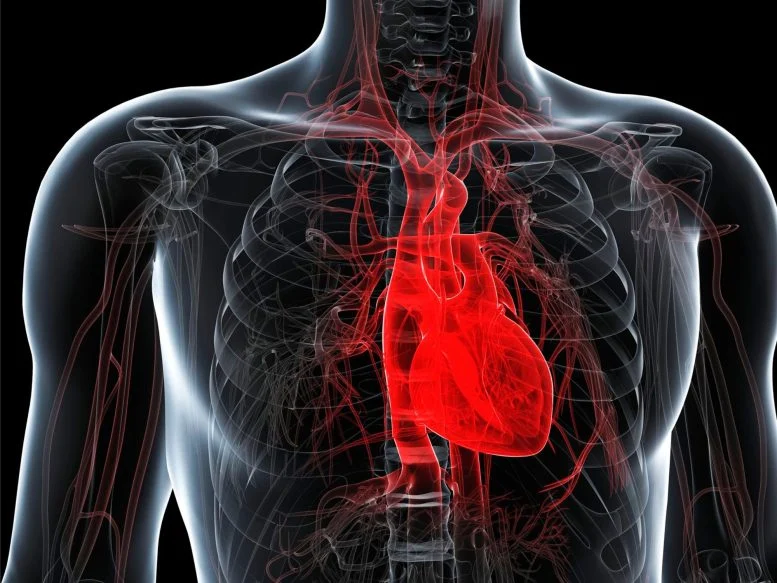

Οι ερευνητές ανακάλυψαν ότι μια διατροφή με βάση τα θρεπτικά συστατικά, με βάση τα φυτά, θα μπορούσε να αποτρέψει και να αναστρέψει μια κρυφή μορφή καρδιακής νόσου σε υπερτασικούς αρουραίους. Μια νέα μελέτη από ερευνητές στο Ινστιτούτο Βιοϊατρικών Επιστημών στο Πολιτειακό Πανεπιστήμιο της Τζόρτζια αναφέρει ότι μια δίαιτα με επίκεντρο τα φρούτα, τα λαχανικά, τους ξηρούς καρπούς και τα όσπρια μπορεί να βοηθήσει τόσο στην πρόληψη όσο και στη βελτίωση των καρδιακών παθήσεων στην […]

Οι επιστήμονες ανακαλύπτουν μια δίαιτα που μπορεί να αποτρέψει και να αναστρέψει έναν βασικό τύπο καρδιακών παθήσεων